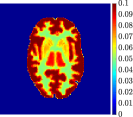

Figure 4, Figure 5, and Figure 6 show the mean images computed over the ten reconstructions obtained by the methods reg-AS-TR, reg-GN, and by the Matlab routine lsqcurvefit implementing a standard Trust-Region-Reflective least-squares algorithm [11, 10]. We used the noise-free IF and the perturbed IF with and of noise, respectively. Figure 7 contains mean and standard deviation values of the kinetic parameters computed over the ten reconstructions and over each one of the four homogeneous regions, for each one of the three noise levels on the IF.

In general, reg-AS-TR and lsqcurvefit seem to provide similar mean reconstructions, although uncertainties associated to lsqcurvefit are significantly bigger. On the other hand reg-GN seems to systematically underestimate the parameter values within region . Furthermore and as expected, for all methods the quality of the parametric reconstructions deteriorates with increasing noise levels; this is more clear from the and parametric images, probably due to the different sensitivities of the data with respect to the model parameters [37]. In reg-GN and lsqcurvefit some artifacts can be observed at the edges of the homogeneous regions, especially around region and region , whereas the effect of regularization in reg-AS-TR results in a reduced presence of artifacts while the structure of the regions is preserved. This general trend is confirmed by the error-bar plots of Figure 7. Finally, the frames in Figure 8 corresponding to reg-AS-TR show a significant improvement of the image quality with respect to what is provided by the other two approaches.